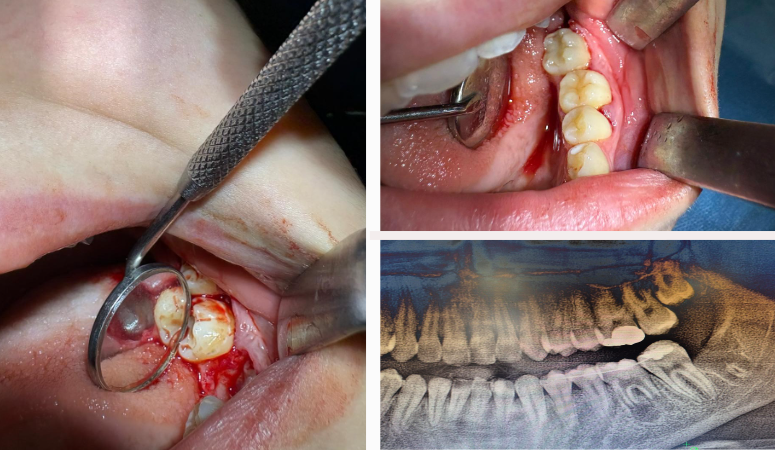

Hastane Başhekimliğinden edinilen bilgilere göre; Genç hastanın ileri düzey çürük nedeniyle tedavi amaçlı olarak bir daimi azı dişi çekildi. Ancak çocuk yaşta çene gelişimi devam ettiği için implant uygulaması gibi klasik tedavi yöntemleri uygun görülmedi. Bu nedenle hastanın kendi ağzında kemik içinde gömülü halde bulunan üçüncü azı dişi (yirmi yaş dişi), uzman ekip tarafından operasyon mikroskobu eşliğinde cerrahi operasyonla çıkarıldı ve hazırlanan yuvaya nakledildi. Ayrıca, dişin daha sağlıklı bir şekilde iyileşebilmesi için çocuğun kendi kanından elde edilen PRF (kişinin kendi kanından elde edilen, hücre yenilenmesini destekleyen doğal bir biyomateryal) nakil işlemi öncesinde hazırlanan yuvaya konuldu.

Karabük ADSEAH Başhekimi Prof.Dr. Ahmet Taylan Çebi’de konuyla ilgili olarak ” Bu özel işlem, hastanın kendi dişi kullanıldığı için hem doğal görünüm hem de fonksiyon açısından büyük avantaj sağlamaktadır. Dişin vücut tarafından kabul edilme ihtimali yüksek olduğu için uzun vadeli başarı oranları da oldukça yüksektir. Hastanın tedavisi, Endodonti Anabilim Dalı öğretim üyesi Doç. Dr. Olcay Özdemir ile Ağız, Diş ve Çene Cerrahisi Anabilim Dalı öğretim üyesi Dr. Öğr. Üyesi Muhammed Abdullah Çege tarafından başarılı bir şekilde gerçekleştirilmiştir.” bilgilerini verdi.